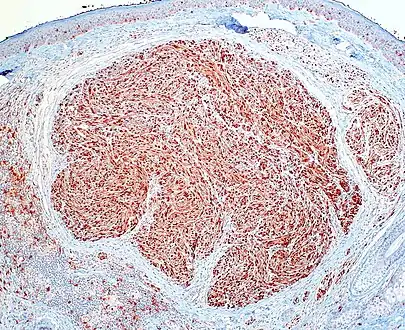

Micrograph of a palisaded encapsulated neuroma

PEN is diagnosed by clinical recognition of the lesion and on subsequent histologic examination. Typically, the lesions are suspected to be schwannomas or neurofibromas clinically with PEN being an incidental finding on histology.[3]

PEN is typically diagnosed in patients between the ages of 40 and 60 years and occurs more frequently in females than males. The diagnosis of PEN may be difficult, even with confirmatory histology, due to its histological similarities with schwannomas and neurofibromas. It is imperative that the correct diagnosis is made the misdiagnosis of a neurofibroma may lead to unnecessary further investigation into associated systemic syndromes such as neurofibromatosis type 1 or multiple endocrine neoplasia syndrome.[3][4]